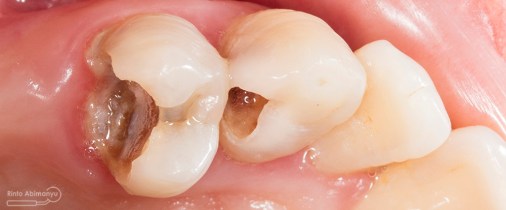

Kasus hari ini ceritanya datang seorang pasien wanita usia sekitar 50 an mengeluhkan gigi2 atas kirinya sering terselip makanan dan terkadang terasa senut-senut…

Pada pemeriksaan intra oral terlihat gigi 23 dan 24 mengalami karies dan cukup banyak sisa makanan terjebak disana…

Pemeriksaan respon dingin pun menunjukkan hasil negatif, untuk menambah data dalam penegakan diagnosis maka dilakukan pengambilan ronsen pada gigi2 tersebut

Terlihat dari ronsen tersebut karies pada gigi 23 24 sudah mencapai pulpa… dari informasi pemeriksaan klinis dan ronsen maka didiagnosis gigi tersebut nekrosis.. Saya jelaskan kepada pasien mengenai kondisi gigi2 nya dan rencana perawatan yang akan saya lakukan…